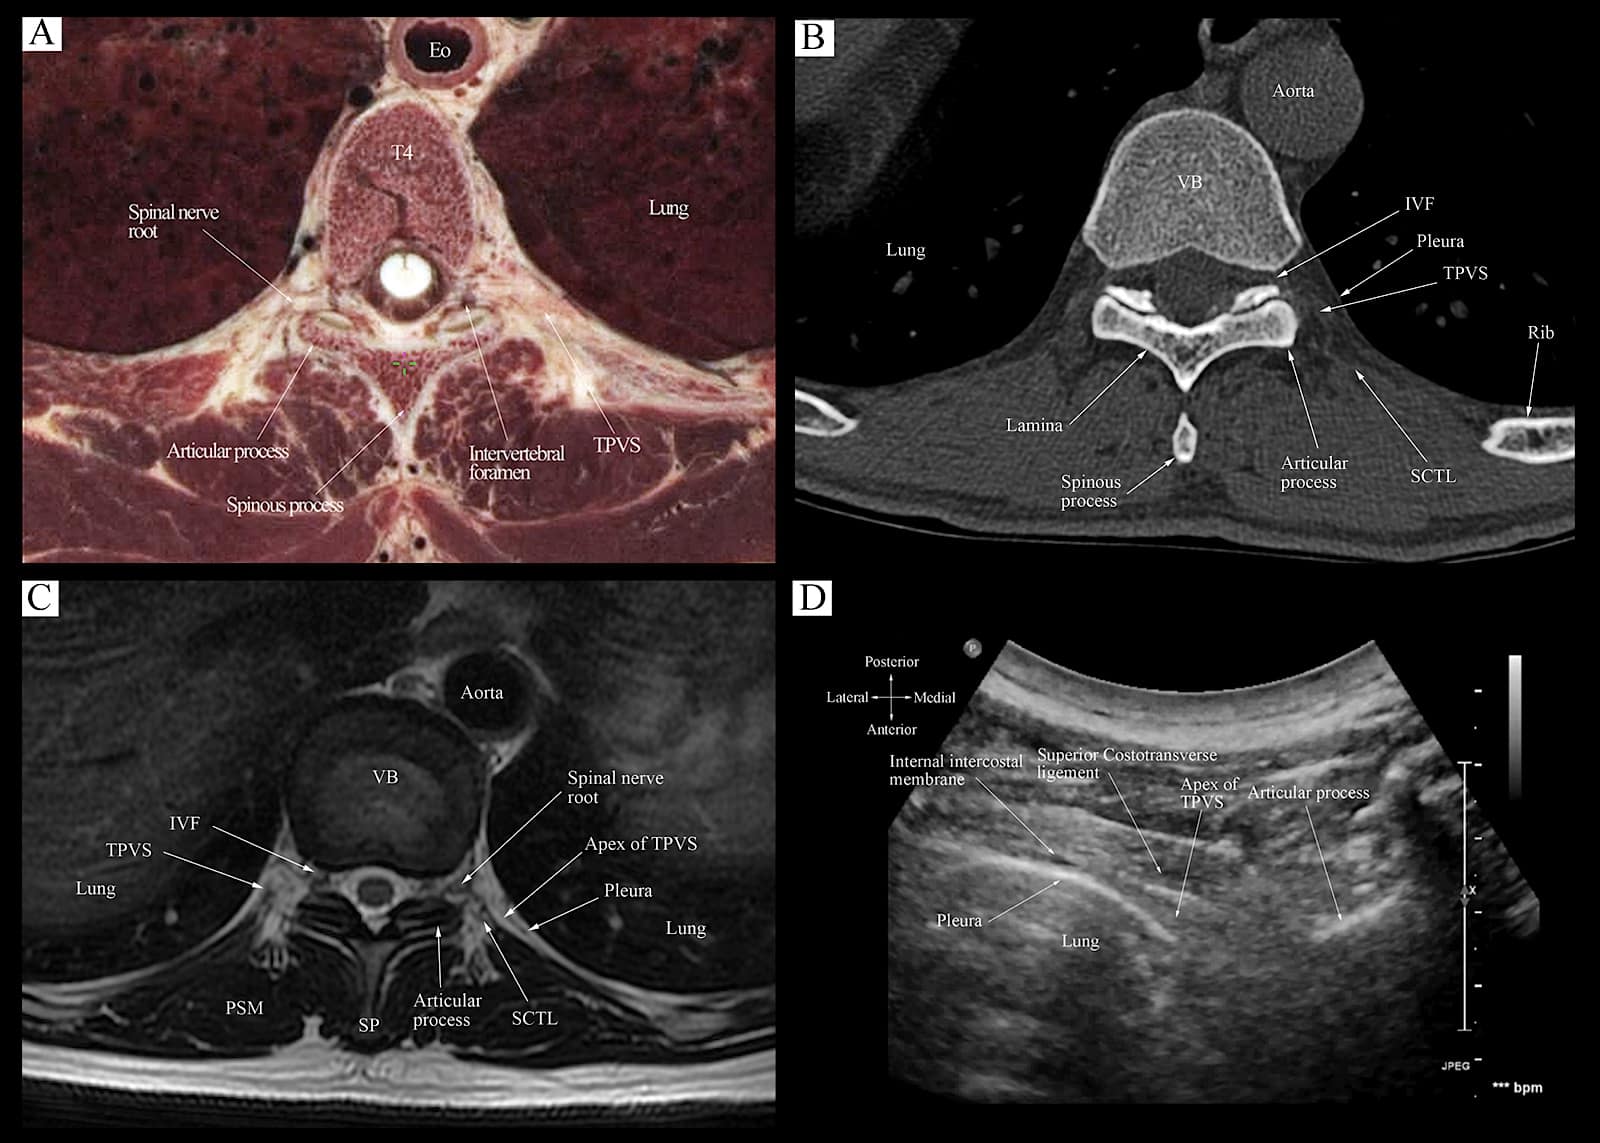

The Transverse Ultrasound Scan Sequence

The target transverse ultrasound window at the level of the IAP is obtained through three sequential steps, over three contiguous osseous anatomical landmarks (Figure 10), at the target vertebral level.11,62,63 The sequential steps are as follows: Step 1 at the transverse process-rib complex level (Figure 10, red box). Step 2 at the transverse process level (Figure 10, blue box), and step 3 at the IAP level (Figure 10, green box). Based on the underlying osseous and musculoskeletal structures, these three ultrasound scan windows produce three distinct sonograms (Figure 9). Correlative cadaver anatomic-CT-MRI and transverse sonograms for steps 2 and 3 of the transverse scan sequence are presented in Figures 11 and 12.

Figure 12. Correlative transverse cadaver anatomic (Fig 12A), CT (Fig 12B), MRI (T1 weighted, Fig 12C), and ultrasound (Fig 12D) images of the thoracic paravertebral region from the level of the vertebral body and inferior articular process corresponding to the level at which the transverse scan is performed (position 3, Fig 10).

TPVS = thoracic paravertebral space, VB = vertebral body, PSM = paraspinal muscle, IVF = intervertebral foramen, SCTL = superior costotransverse ligament, SP = spinous process

Reproduced with permission from the Department of Anesthesia and Intensive Care, The Chinese University of Hong Kong, Faculty of Medicine, www.aic.cuhk.edu.hk/usgraweb.